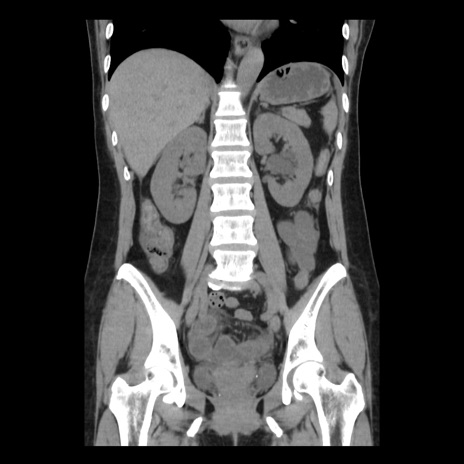

症例10(冠状断像)

【症例】 50歳代女性

【主訴】 腹痛

【現病歴】前日生レバーを食べた。今朝に排便あり。 昼前に突然発症の腹痛を生じ、当院救急外来を受診した。

【既往歴】 子宮筋腫にてで子宮全摘後

【身体所見】 意識清明、腹部:平坦、軟、下腹部やや左を中心に圧痛・反跳痛あり、筋性防御あり

【データ】WBC 7800、CRP 0.07